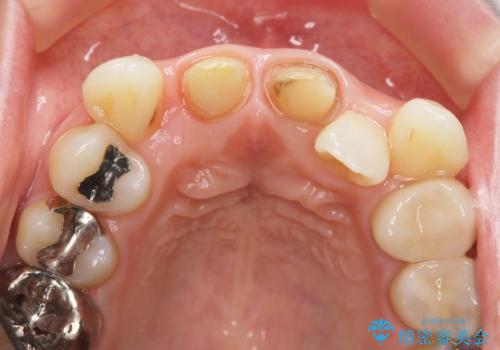

X線写真より、充填剤の突き出た状態の根管治療の再治療を行い、セラミック治療を計画すると同時に、

歯ブラシがしづらく虫歯の原因となっている歯の位置の悪い右上側切歯の抜去を行います。

清掃を難しくしている歯を抜去することで虫歯の再発を防ぐような治療方針としました。